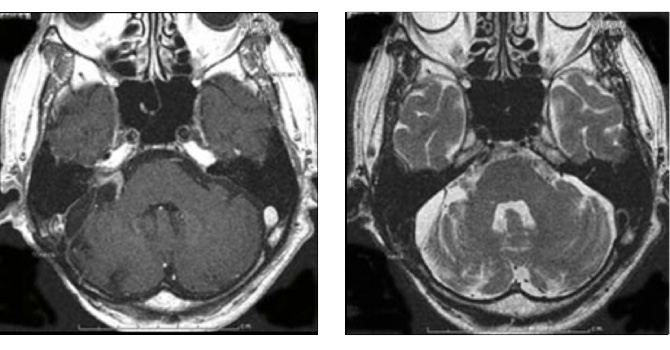

図3:50代男性 ガンマナイフ後3年半で拡大

(左図)ガンマナイフ時(中図)3年半後(右図)手術後 術後4年経過するも再増大なし

図3はガンマナイフ後、残念ながら増大してしまった50代男性の腫瘍です。聴覚はすでに失われておりましたので、注意深く顔面神経を保護しつつ手術を行い、95%摘出しました。術後問題なく社会復帰されています。